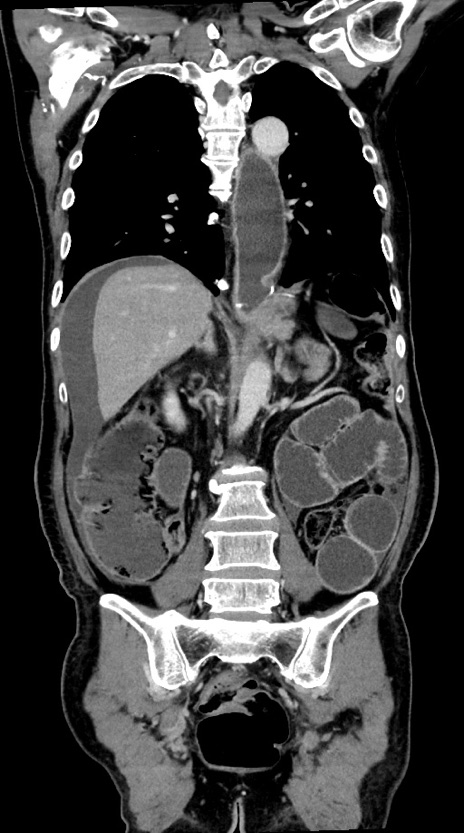

症例28(冠状断像)

【症例】60歳代男性

【主訴】嘔吐

【現病歴】胃癌にて胃全摘後。食思不振が悪化し、夜中に嘔吐することがある。

【既往歴】胃癌、胃全摘、脾摘、胆摘後

【データ】WBC 5900、CRP 10.56